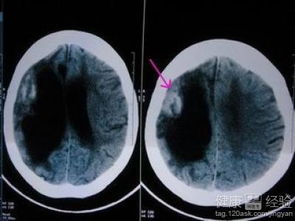

腦梗死是因腦部的血液供應障礙而造成局部腦組織缺血,因為缺血缺氧,而造成的腦組織的壞死,引起了一系列的神經功能的障礙,這一種綜合癥稱為腦梗死。腦梗死是目前最常見的一種疾病,那么它的致殘率,致死率,都非常高,剛才講到腦血管引起的血液障礙,那么這個血管包括動脈血管和靜脈血管。腦血管動靜脈血管分又為顱內的腦血管,和顱外的腦血管,這些血管造成的狹窄和閉塞,都可以造成血液和血流的障礙,而引起腦組織的缺血缺氧。